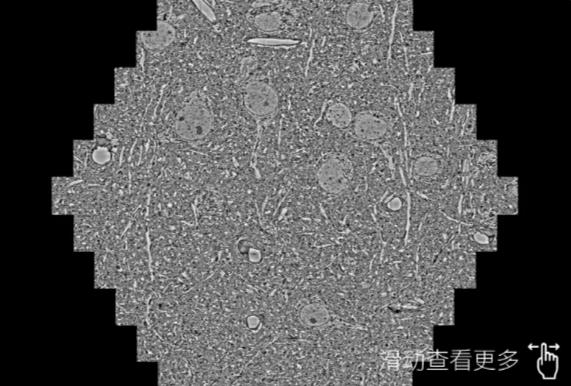

鼠脑切片。左图使用南平蔡司南平扫描电镜MultiSEM706对165μmx143pm面积区域成像,耗时仅需1.5秒。右图为鼠脑切片中30μm区域放大效果。样品由芝加哥大学B.Kasthuri提供。

使用蔡司高速南平扫描电镜MultiSEM对1mm²人脑皮层组织进行高分辨成像,并对其中的各种细胞结构进行三维重构分析。左图展示了2x3mm²组织平面中锥体神经元的三维重构效果。右图显示了局部体积神经元三维重构。图像由哈佛大学chtman实验室提供,渲染图由D. Berger 制作。